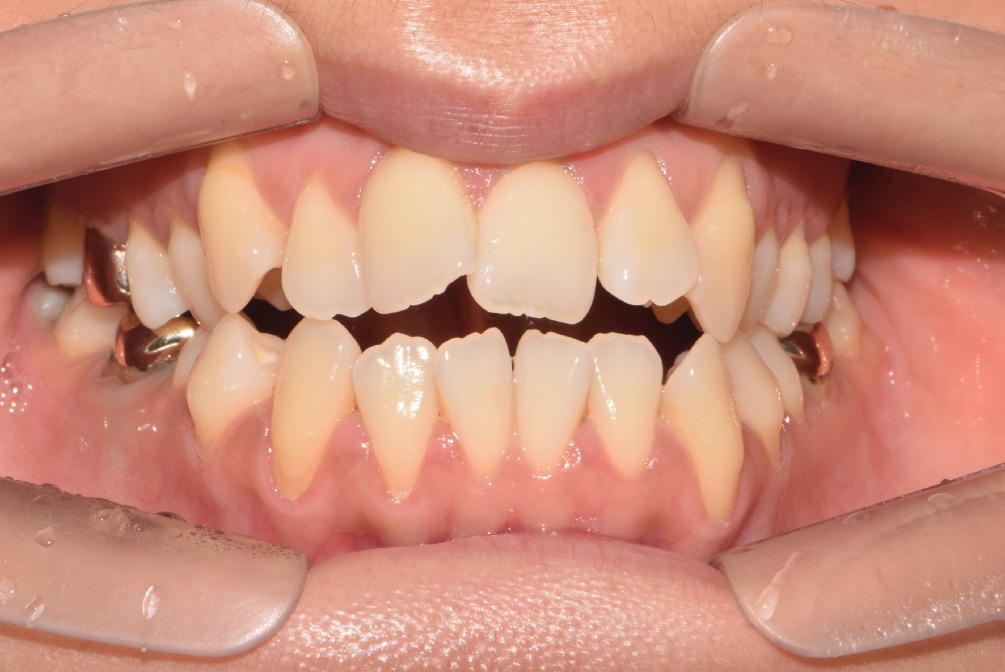

2. 방사선 사진 (파노라마 사진) 1장 & 입안 사진 촬영 및 구강스캔을 힙니다.

그리고 환자분 입안 사진을 찍어서 거울로만 보던 입안 상태를 잘 확인할 수 있게합니다.